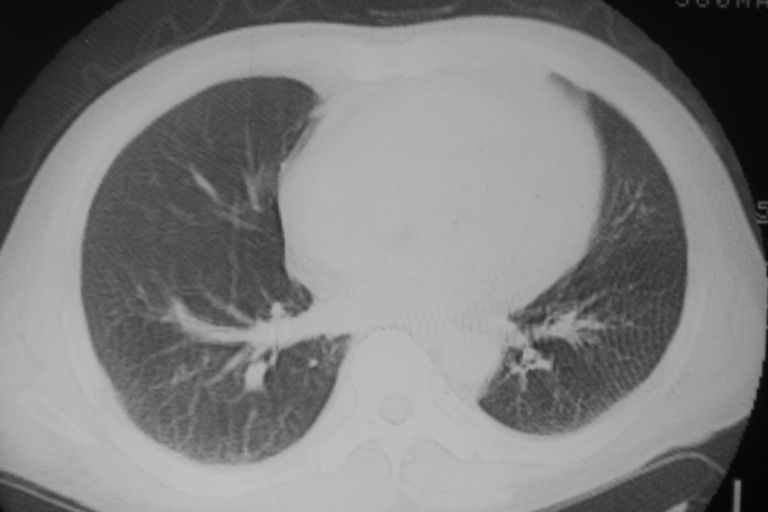

患者 男 50岁 无痛性咯血3天,无其他不适.

左下肺结节状软组织密度影,边缘有毛刺,考虑周围型肺癌。

1 左肺下叶基底段见两结节软组织密度灶, 肺窗边缘见有毛刺征像, 不能排除占位. 2 建议结合临床治疗一周后ct随访在看其结果.

临近胸膜增厚,病变周围肺不清,稍有分叶。结节密度略高,肺、纵隔窗差异不大,肺癌待排。前方还有一个

左下肺结节状软组织密度影,一个边缘有卫星病灶,邻近胸膜增厚.另一个有毛刺.心影周围水样密度影环绕.考虑:

1.肺癌可能.肺tb待排.

2.左侧胸膜增厚.心包积液.